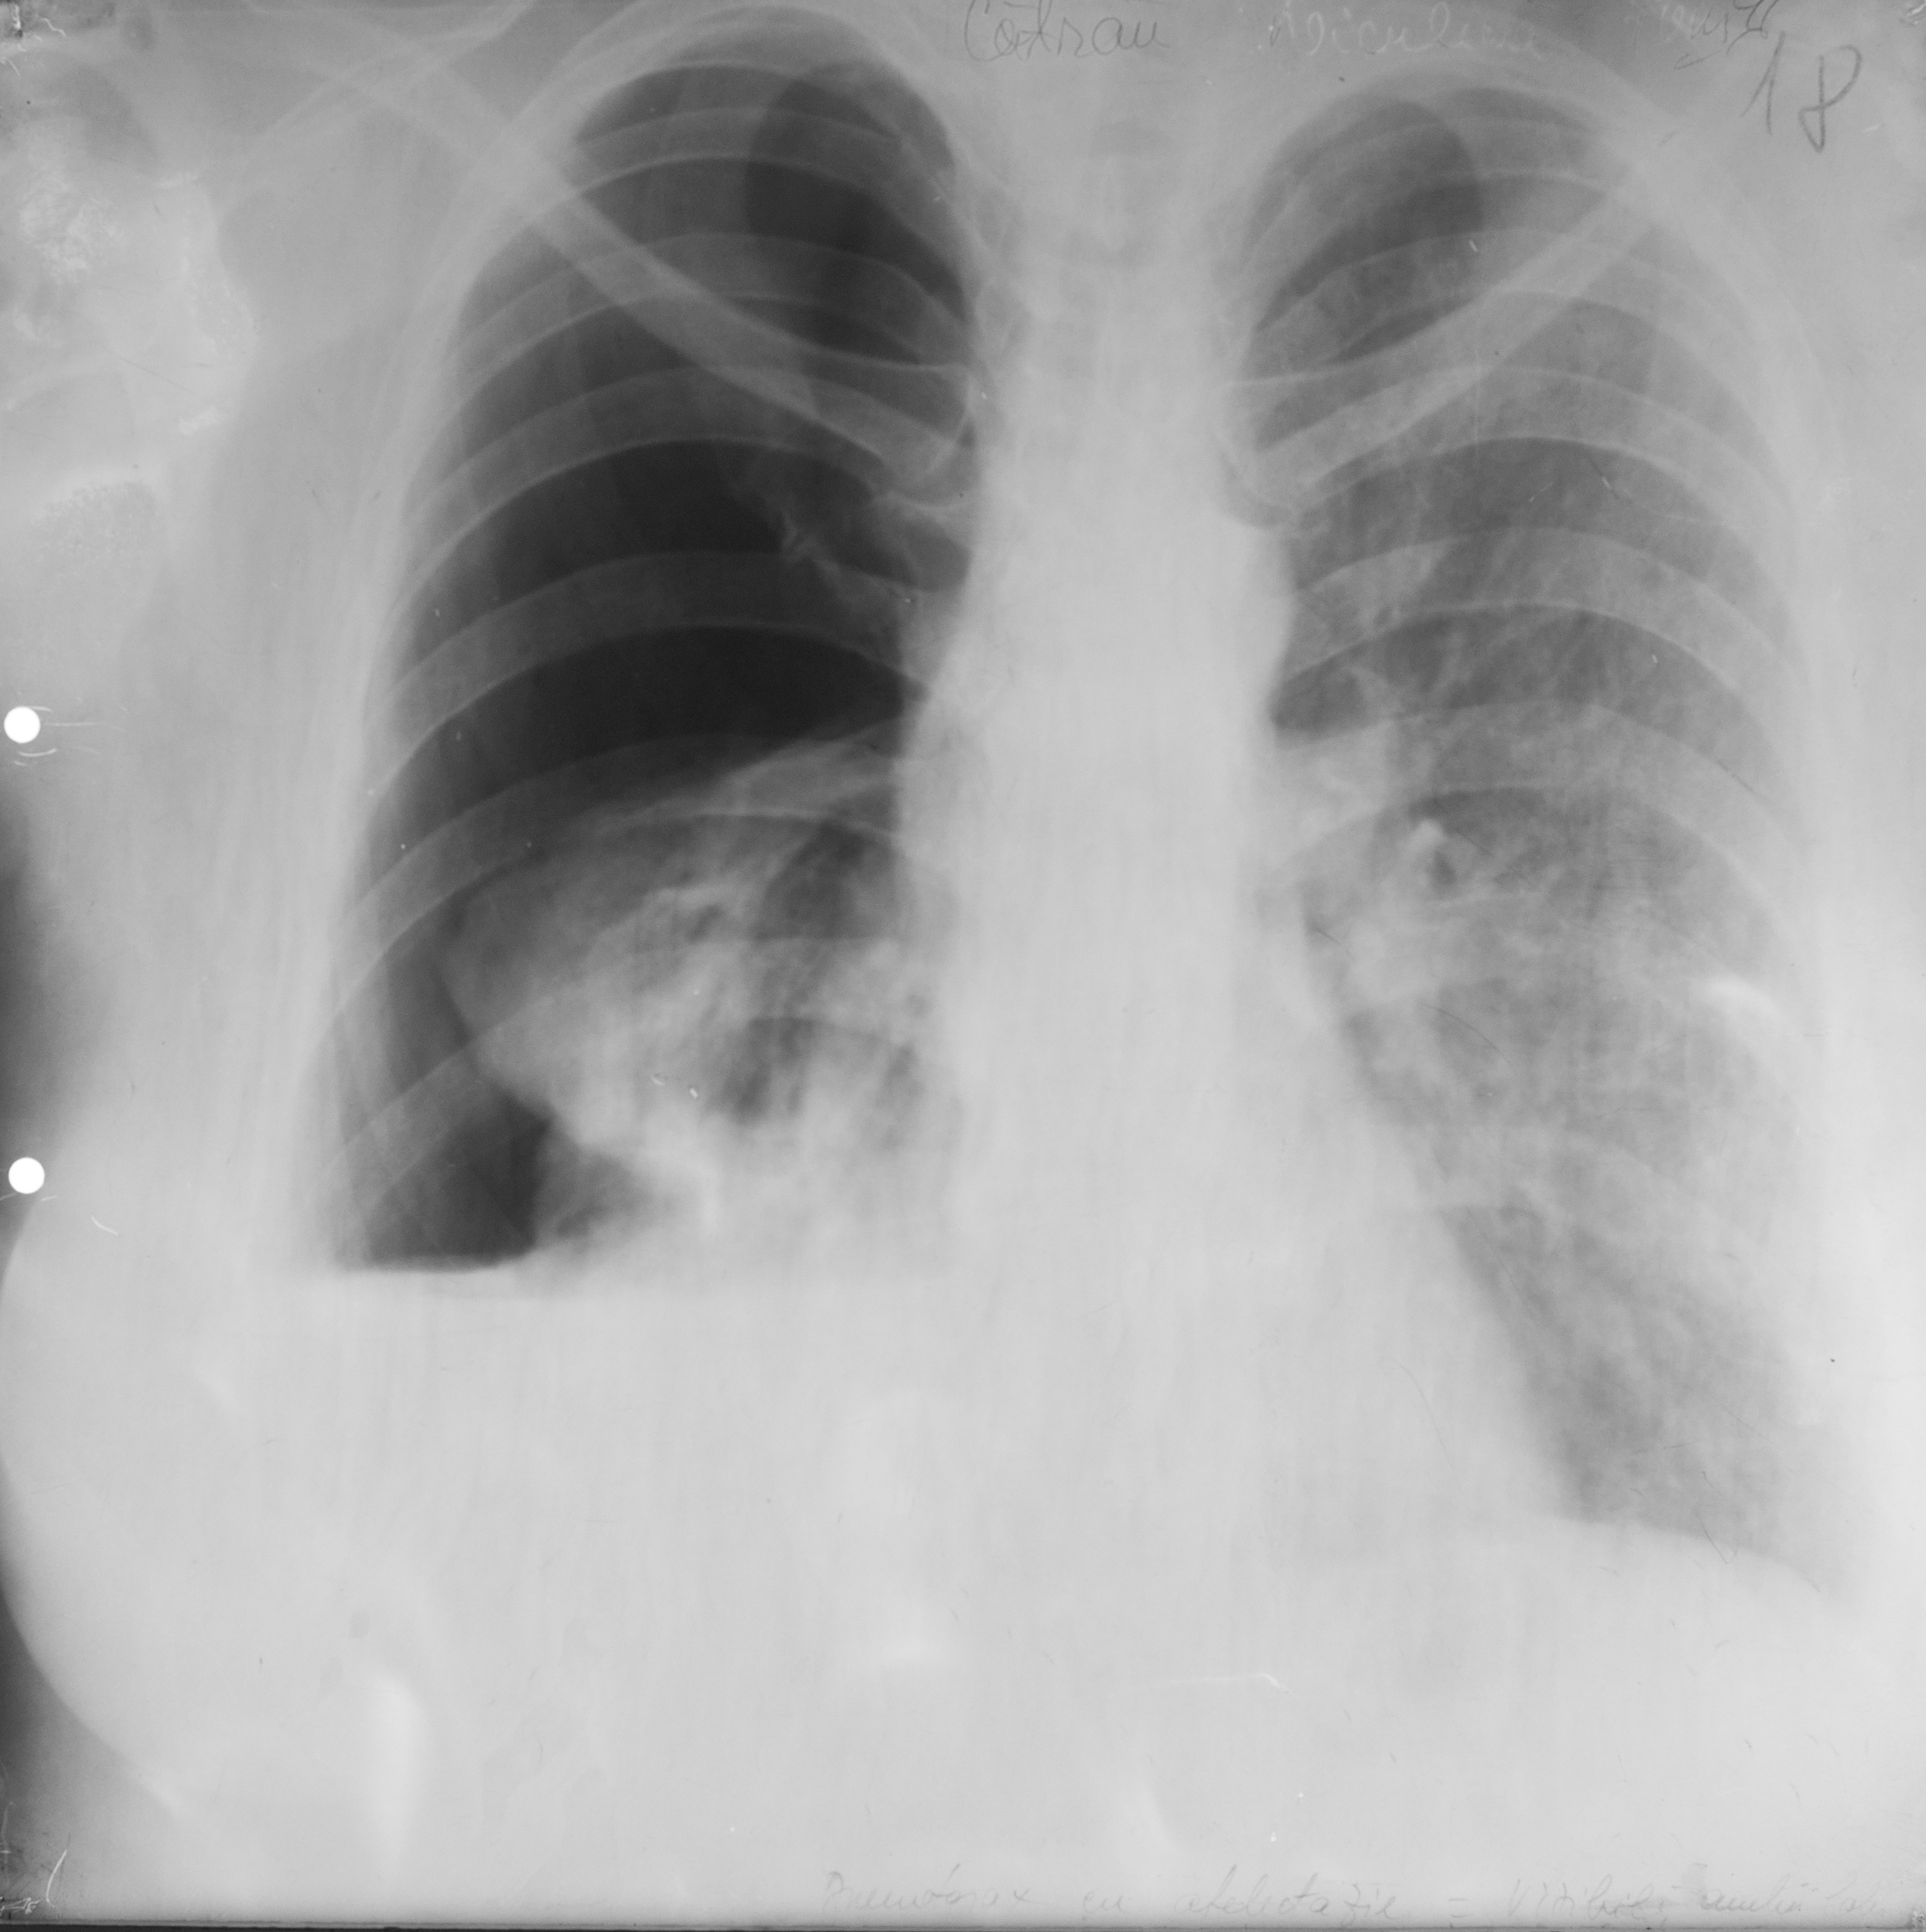

Rx toraco-mediastino-pleuro-pulmonară – macroopacitate,problema se pune la localizare : in campul pulmonar apartinand plamanului sau apartinand peretelui toracic – celebrul semn al lui Bernu – opacitate care este tangenta la mediastin,daca face un unghi obtuz cu peretele (unghi de racordaj obtuz),apartine peretelui toracic,iar daca unghiul este ascutit apartine parenchimului pulmonar

Rx toraco-mediastino-pleuro-pulmonar - aici vedem o opacitate tot similară cu aceea,tot net liniar delimitata,dar de data aceasta unghi de racordaj ascutit,inseamna ca apartine campului pulmonar

Rx toraco-mediastino-pleuro-pulmonar – opacități multiple de dimensiuni variabile situate mai degraba la bazele pulmonare,de intensitate medie-slaba,unele mai intense,altele mai putin intense,contururile plu ? – sunt procese de condensare avand in vedere aspectul acesta plu si undeva situat bazal – probabil bronho-pneumonie